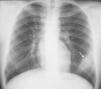

Niño de 13 años, que consulta por dolor desde hace 4 meses en hemitórax izquierdo, irradiado a la zona posterior, relacionándolo con el esfuerzo y mejorando con el reposo. La exploración era dolorosa a la palpación profunda de la región media costal izquierda. Se le realizó Rx simple de tórax (fig. 1), objetivándose una tumoración extrapulmonar izquierda en relación con el 7° arco costal, que no erosiona. La resonancia magnética en secuencia T1 (fig. 2) mostró una tumoración de alta intensidad de señal, sólida, homogénea en íntimo contacto con el 7° arco costal, que no presentaba matriz ósea, y con bordes obtusos característicos de las lesiones extrapleurales. El hemograma y la bioquímica realizada fueron normales. El paciente fue intervenido realizándole exéresis en bloque del tumor y 7.° arco costal. El resultado anatomopatológico fue de tumor neuroectodérmico primitivo (tumor de Askin).